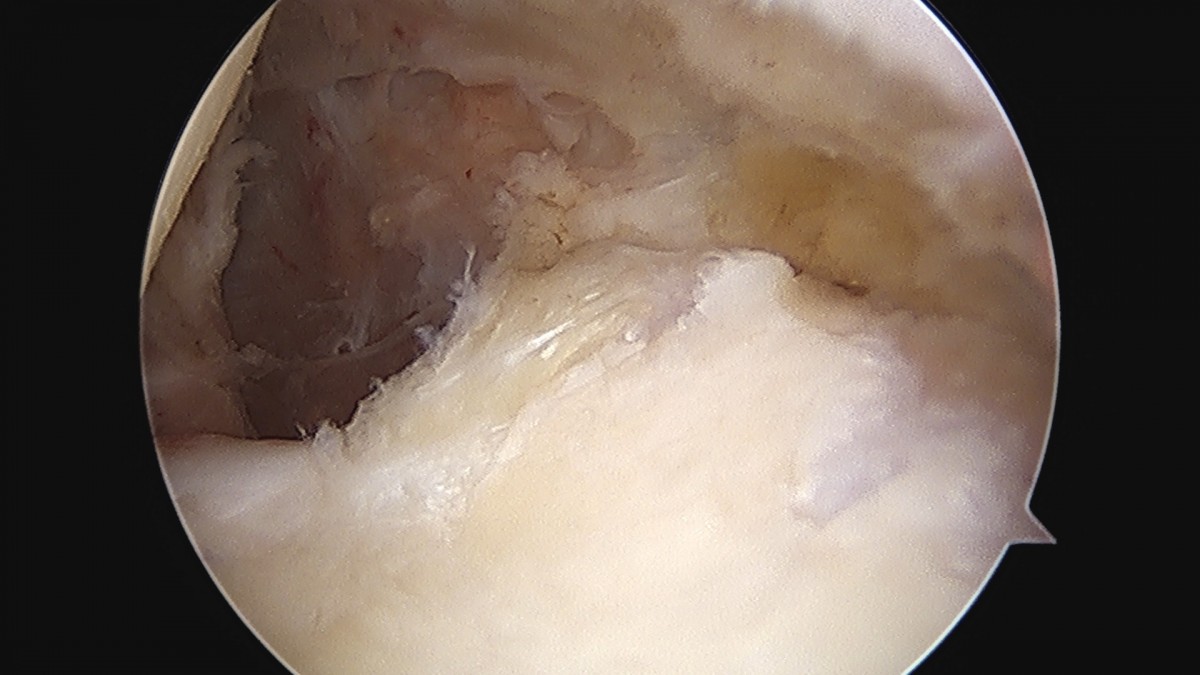

이재상원장님 어깨 이두박건 절제술 정하O 환자

dae765e4d9ac96aee867c9d6292d8784_1758006930_754.jpg